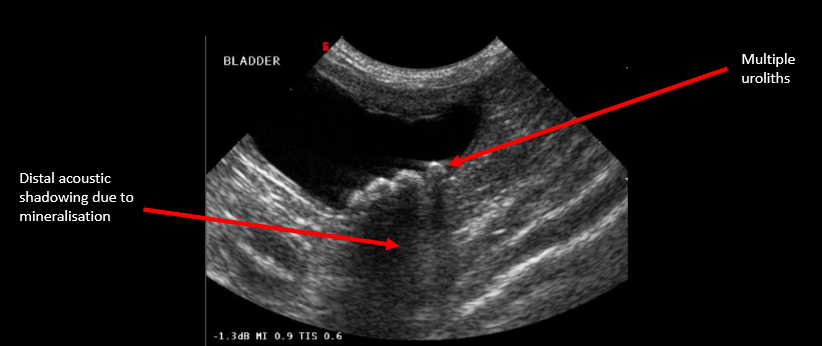

Label this ultrasound

Identify this structure What pathology is present?

Label this structure What pathology is present?